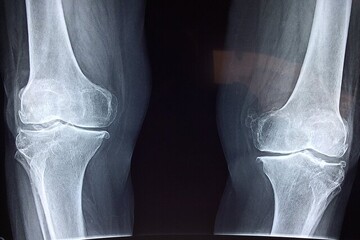

فوق تخصص بیماری‌های روماتولوژی با اشاره به اهمیت پیشگیری و تشخیص زودهنگام پوکی استخوان گفت: این بیماری به کاهش مواد معدنی و آلی در بافت استخوان گفته می‌شود و متأسفانه اصلی‌ترین علامت آن، بی‌علامتی است؛ یعنی در بسیاری از موارد بیمار هیچ نشانه‌ای ندارد و استخوان‌ها به‌تدریج و بی‌صدا دچار ضعف و پوکی می‌شوند، همانند موریانه‌ای که چوب را آهسته می‌خورد.